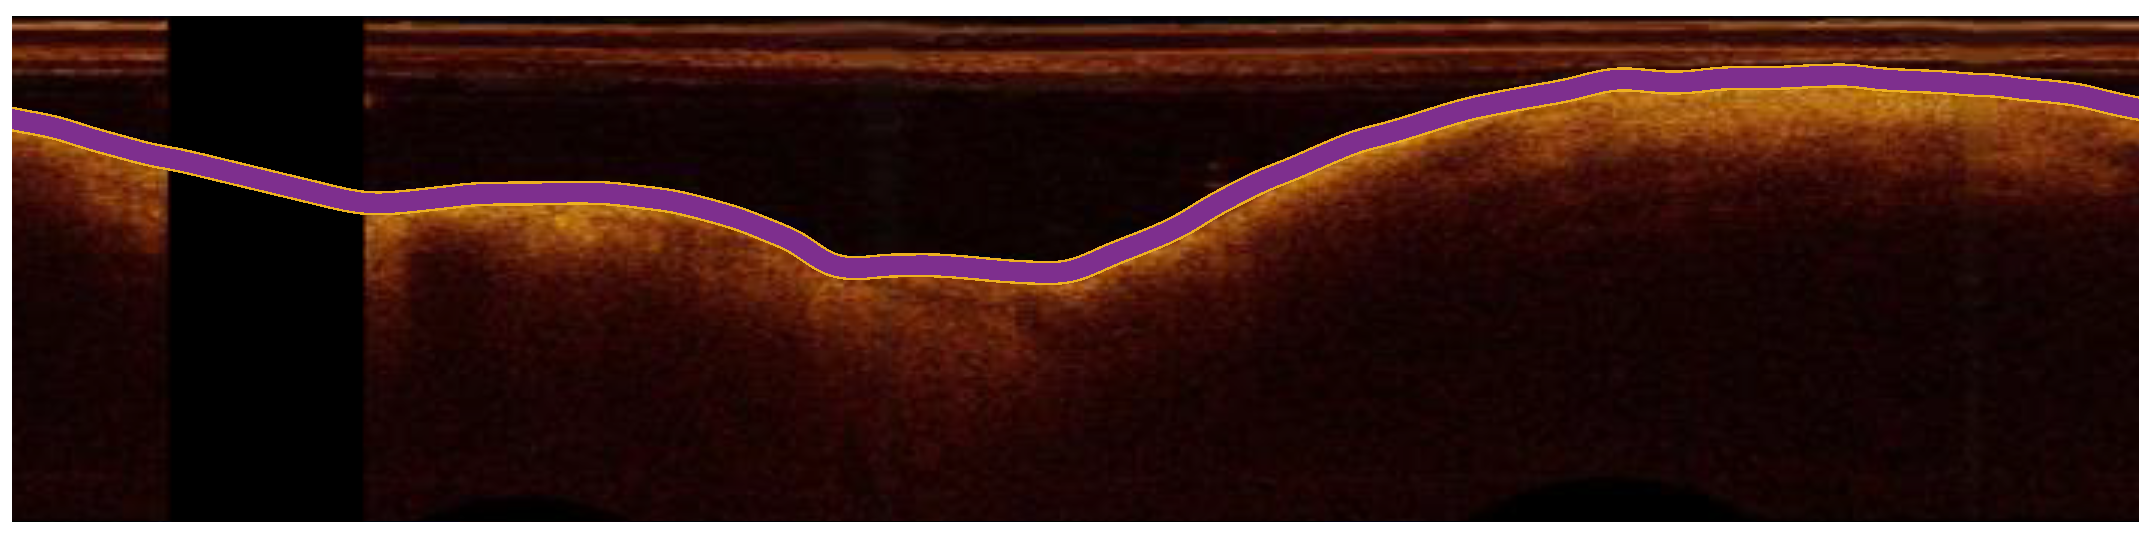

3.4. Segmentation of the Arterial Wall

After preprocessing, the ARC-OCT algorithm was applied for the delineation of lumen-wall borders [30]. ARC-OCT includes mainly OCT-specific (depth-resolved) transformation of images, thresholding, morphological operations and contour smoothing. The lumen-wall border was not defined in A-lines with guide-wire artifacts, but it is estimated by the neighboring parts of the border. However, image parts influenced by guide-wire artifacts were excluded from further examination in this work. In Figure 2, the result of the lumen segmentation algorithm is presented.

Figure 2. The detection of the lumen-wall border (shown in purple) in an OCT image (in polar coordinates) of the artery.